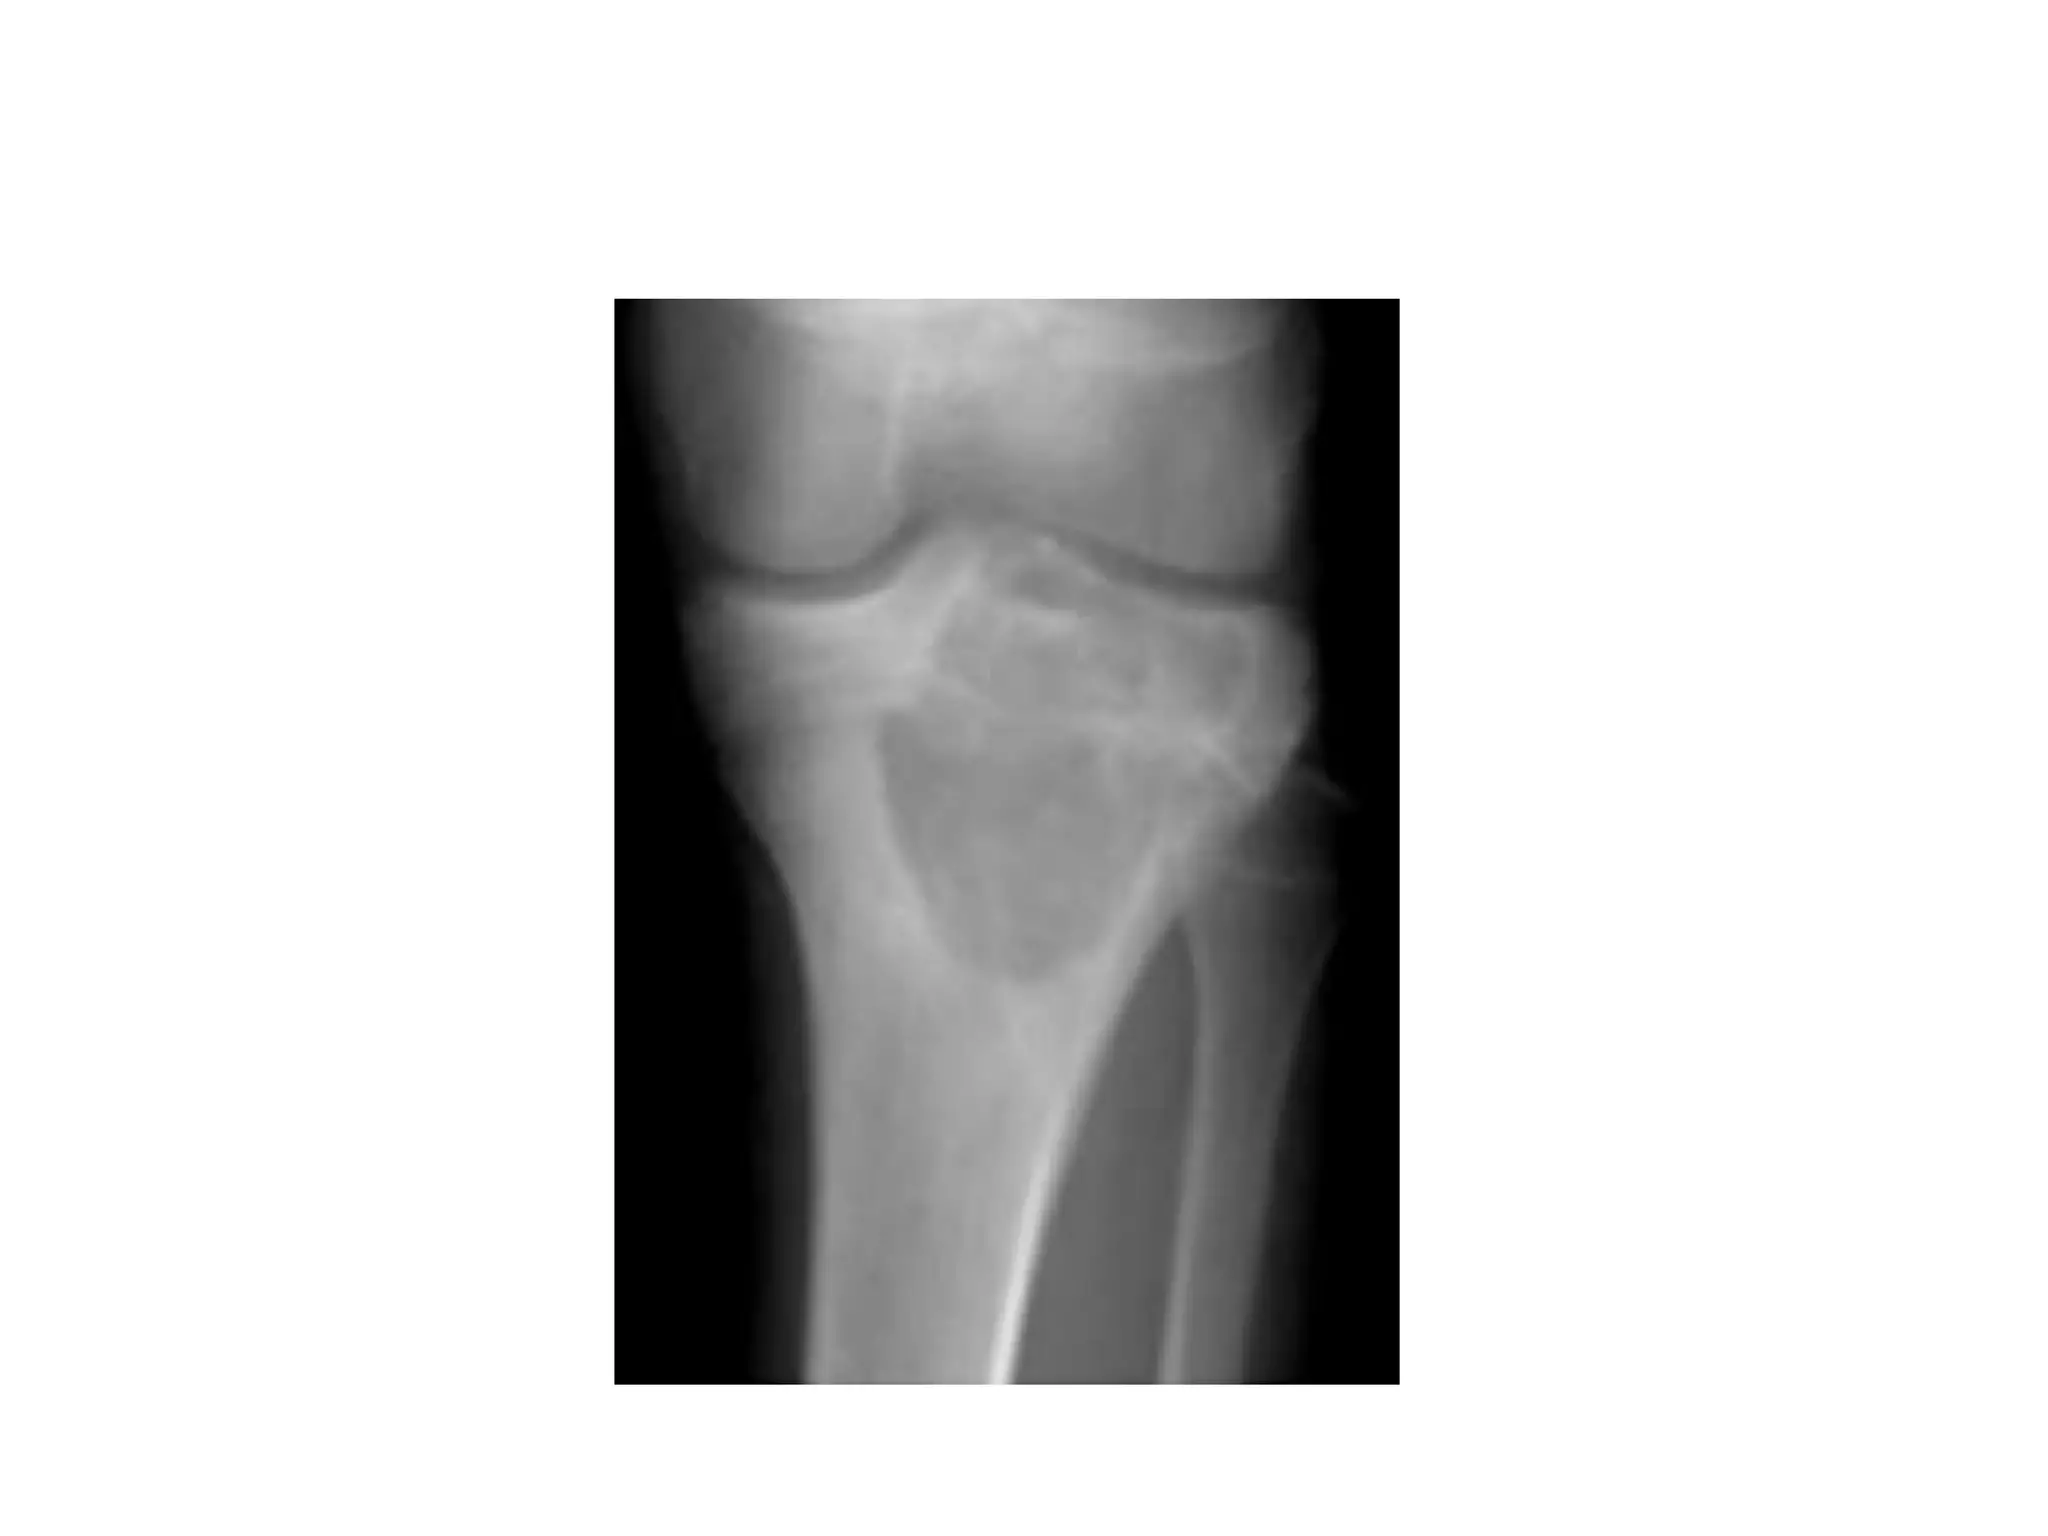

CHONDROBLASTOMA

• Benign tumor of childhood

• Mostly epiphyses, usually at end of long bones

• Typically presents with pain and ocassionally

cause joint effusion and stiffness.

• On X ray: round or oval lesion ranging from 1

to 7 cm on x ray.

• Histologically: appears as “wet-sawdust” with

areas of chondroid matrix,calcification and

haemorrhage.

• Presence of chicken- wire calcification is

pathognomic.

• Treatment: simple curettage with or without

bonegraft.

• Recurrence: 10% of cases.